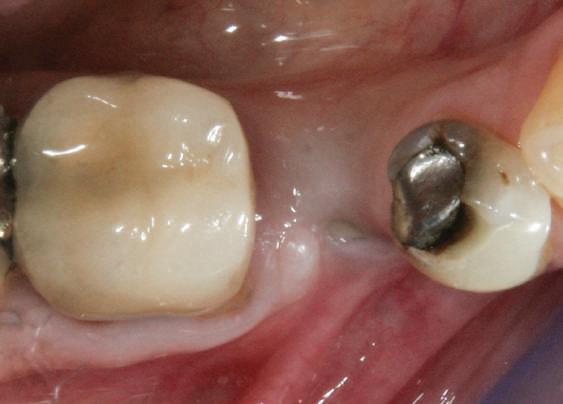

Alt caz (1) Figurile

4. După osteointegrarea implantului 2.4., s-a observat recesia în etapa de amprentare a implantului 2.5.; s-a decis reprepararea marginilor bontului individualizat CAD/CAM 2.4. Înainte de preparare s-a aplicat şnur de retracţie pentru a evita lezarea ţesutului şi a îmbunătăţi vizibilitatea dintelui 2.3. şi a marginii bontului implantar individualizat. Aşa cum era de aşteptat, recesia a fost mai mare de-a lungul versantului distal al bontului 2.4. adiacent locului de extracţie vindecat/cu implantul mai nou.

5. Bontul individualizat aplicat (2.5.) cu bontul repreparat anterior (2.4.). Nu a survenit recesie nouă de o perioadă de peste 3 ani.